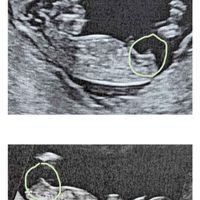

Apro in puntissima di piedi questo post..dopo un aborto di 4 anni fa e una diagnosi di infertilità maschile,mi ritrovo incinta di 4 settimane con una totale assenza di sintomi e tanta paura❤️...